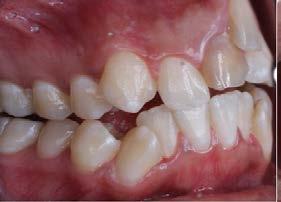

en mi personalidad”. Como antecedentes médicos y familiares refiere 2 traumatismos fuertes en su infancia que causaron avulsión de los dientes 11 y 21, clicking y crepitus en la articulación temporomandibular (ATM).

En su análisis facial la paciente presentó un perfil convexo con un tercio inferior aumentado, patrón dolicocefálico severo de VERT, sonrisa gingival e incompetencia labial (Figura 1 A). Durante la exploración intraoral encontramos mordida abierta anterior con apiñamiento severo superior (-13mm) e inferior (-11.5mm), líneas medias desviadas y no coincidentes con la línea media facial, el diente 11

mutilado y con tratamiento de conducto inconcluso, overbite -3mm y overjet 8mm (Figura 1 B).

En la ortopantomografía se observó asimetría de las ramas mandibulares, reabsorción radicular severa del diente 21, extrusión de incisivos inferiores y presencia de los dientes 18, 28 y 48 (Figura 2 A). La radiografía lateral de cráneo nos permitió realizar el análisis cefalométrico de Ricketts en el cual se confirmó la clase II esqueletal, el biotipo dolicofacial y la retrusión mandibular (Figura 2 B y C y Tabla 1).